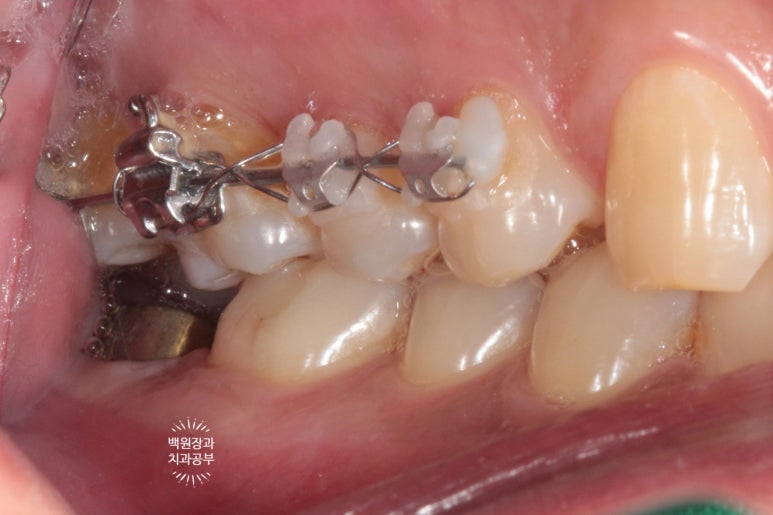

보시면 오른쪽 위 치아 4개에 교정장치가 붙어있는 것을 보실 수 있을거에요.

스트라우만 임플란트를 이용한 임플란트 1차수술을 시행하였습니다.

교정치료가 끝나기 약 2달 전이었습니다.

오른쪽 아래 두번째 큰어금니 자리에 스트라우만 임플란트로 임플란트 1차수술을 해드렸습니다.

사용된 스트라우만 임플란트 모델은 SLA Roxolid Standard plus 4.8WN x 8mm 로,

먼저 맞춤형 지대주를 연결해 줍니다.

보시면 위 어금니에는 아직도 교정장치가 붙어있고,

아래 어금니는 지대주가 설치된 것을 보실 수 있을거에요.